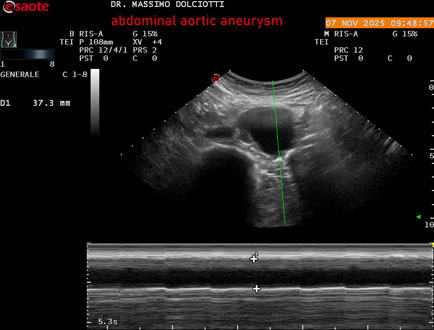

Data inserimento: 11/11/2025

Ecografia del: 07/11/2025

Strumento: Esaote MyLab Eight

Sonda: Convex Multifrequenza 1-8 MHz

Età Paziente: M 60 anni

Motivazione dell'esame: follow up per aneurisma dell'aorta addominale.

Commento all'esame: le immagini ed il video documentano la presenza dell'aneurisma dell'aorta addominale sotto-renale, con diametro antero-posteriore massimo documentato di 47 / 48 mm.

Conclusioni: aneurisma dell'aorta addominale in follow up (abdominal aortic aneurysm follow-up).

Presentazione: Dr. Massimo Dolciotti - Ancona